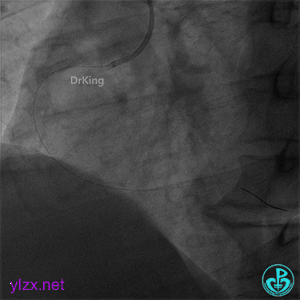

右冠脉近段植入1枚4.0×24mm支架,后扩张后造影示前向血流TIMI 3级。

患者胸痛症状缓解,转入CCU进一步治疗。